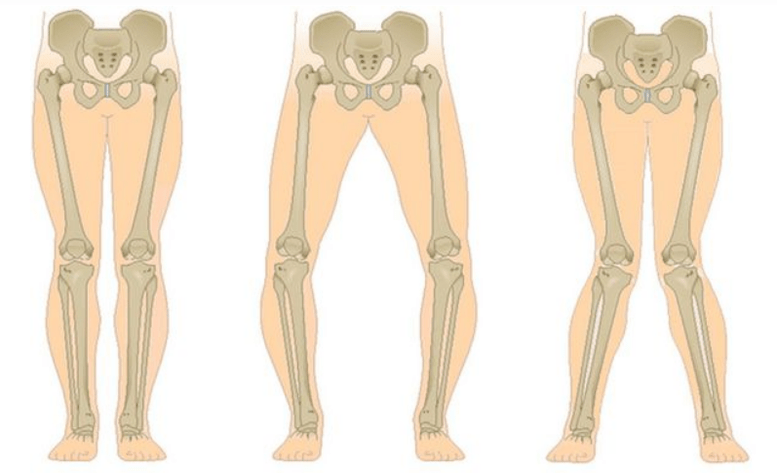

Paskutinė gonartrozės stadija išsiskiria tuo, kad skausmas tampa beveik nuolatinis, sukeliantis nerimą ne tik vaikštant, bet ir ramybėje, ir net naktį, kai ligoniams tenka ieškoti patogios pozos miegoti. Judėjimas ribotesnis: sunku visiškai sulenkti ir ištiesinti koją. Sąnarys deformuojasi ir padidėja tūris. Dažnai stebima kojų (X formos) arba varus (O formos) deformacija. Eisena tampa nestabili ir banguoja. Sunkiais atvejais reikia lazdelės ar ramentų.

Priklausomai nuo pažeistų sąnarių skaičiaus, išskiriama vienpusė ir dvišalė gonartrozė.